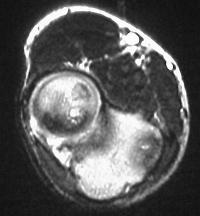

MRI shows an osteochondral sequestrum of the anterior capitellum:

Treatment options? Do nothing, Open reduction and bone graft, sequestrum excision or radial head excision. In this case, at surgery, the loose articular fragment was too thin to allow reliable fixation, and was simply excised.